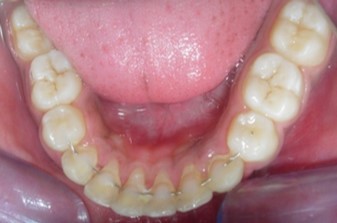

Figure 1g.Pre-treatment intra-oral-Upper occlusal

Figure 1h.Pre-treatment intra-oral-Lower occlusal

The maxillary arch was V-shaped with severely proclined and rotated maxillary incisors with a palatally placed 12. The mandibular arch was U-shaped with severe crowding of mandibular incisors, with 43 partially erupted and buccally placed with transpositioned 42 and 43, with 42 mesiolingually rotated, 33 distolingually rotated and 34 distolingually rotated and buccally placed.

Severe increase in overjet and deep bite were both observed. The maxillary midline coincided with the skeletal midline but the mandibular midline was shifted to the right side by 1 mm. Bilateral maxillary posterior crossbite was also observed. On right side the molar relation was Class I and on the left side it was Class II. The canine relation was Class II on the left side and the curve of Spee was increased.